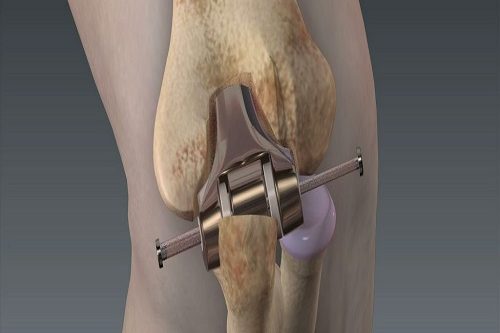

Diz Artroskopisi Nedir? Diz artroskopisi, diz bölümlerinin iç bölümünün küçük bir kamera (artroskop) ile girilerek yapılan cerrahi bir işlemdir. Bu işlem, iç dizinin daha ayrıntılı ve tedavisi için kullanılır. Artroskop, cerrahın dizinin içindeki yapıların net bir şekilde görülmemesini sağlar. Amacı ve Hedefleri Tanısal Amaç : Dizdeki kesin teşhisini koymak için kullanılır. Bu, menisküs yırtıkları, bağ…